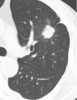

Upper lung disease

Restrictive lung diseases are a category of extrapulmonary, pleural, or parenchymal respiratory diseases that restrict lung expansion, resulting in a decreased lung volume, an increased work of breathing, and inadequate ventilation and/or oxygenation. Pulmonary function test demonstrates a decrease in the forced vital capacity. [Source: Wikipedia ]